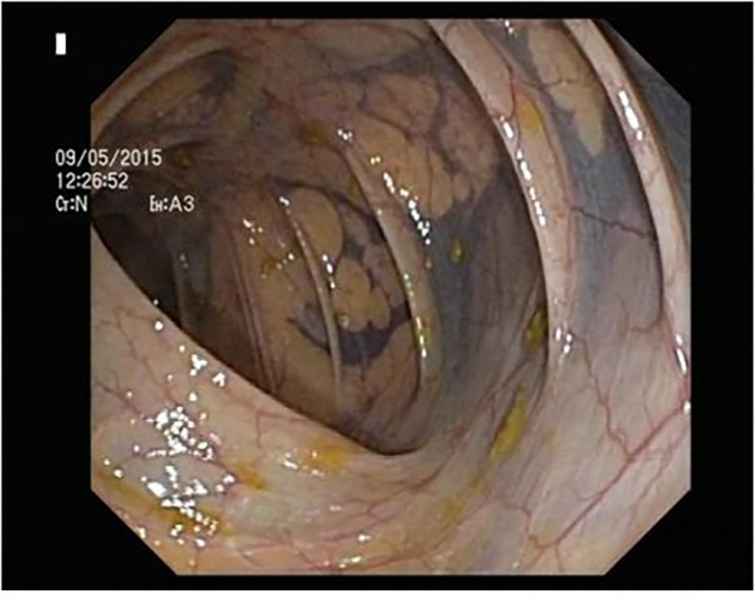

An unusual cause of upper gastrointestinal bleeding and small bowel obstruction

An unusual cause of upper gastrointestinal bleeding and small bowel obstruction

Maria Pia Costa Santos, Alexandre Ferreira, Vera Silveira, Luísa Glória, Marília Cravo

A 58-year-old black female, born in Angola, presented with melena, vomiting and a 7-year history of a right thigh mass that progressively increased in size. Her laboratory tests revealed iron deficiency anemia (hemoglobin 4.4g/dL). Computed tomography showed a large solid lesion in the right thigh, multiple smaller lesions in the lungs, pancreas and uterus, focal thickness of the small bowel wall and jejunal intussusception. Upper gastrointestinal endoscopy revealed multiple ulcerative lesions with elevated edges throughout the second and third portions of the duodenum, with 10-20 millimeters, without hemorrhagic stigmata. The histology of the duodenal and thigh lesions revealed a leiomyosarcoma.

An unusual cause of upper gastrointestinal bleeding and small bowel obstruction

Fotografia